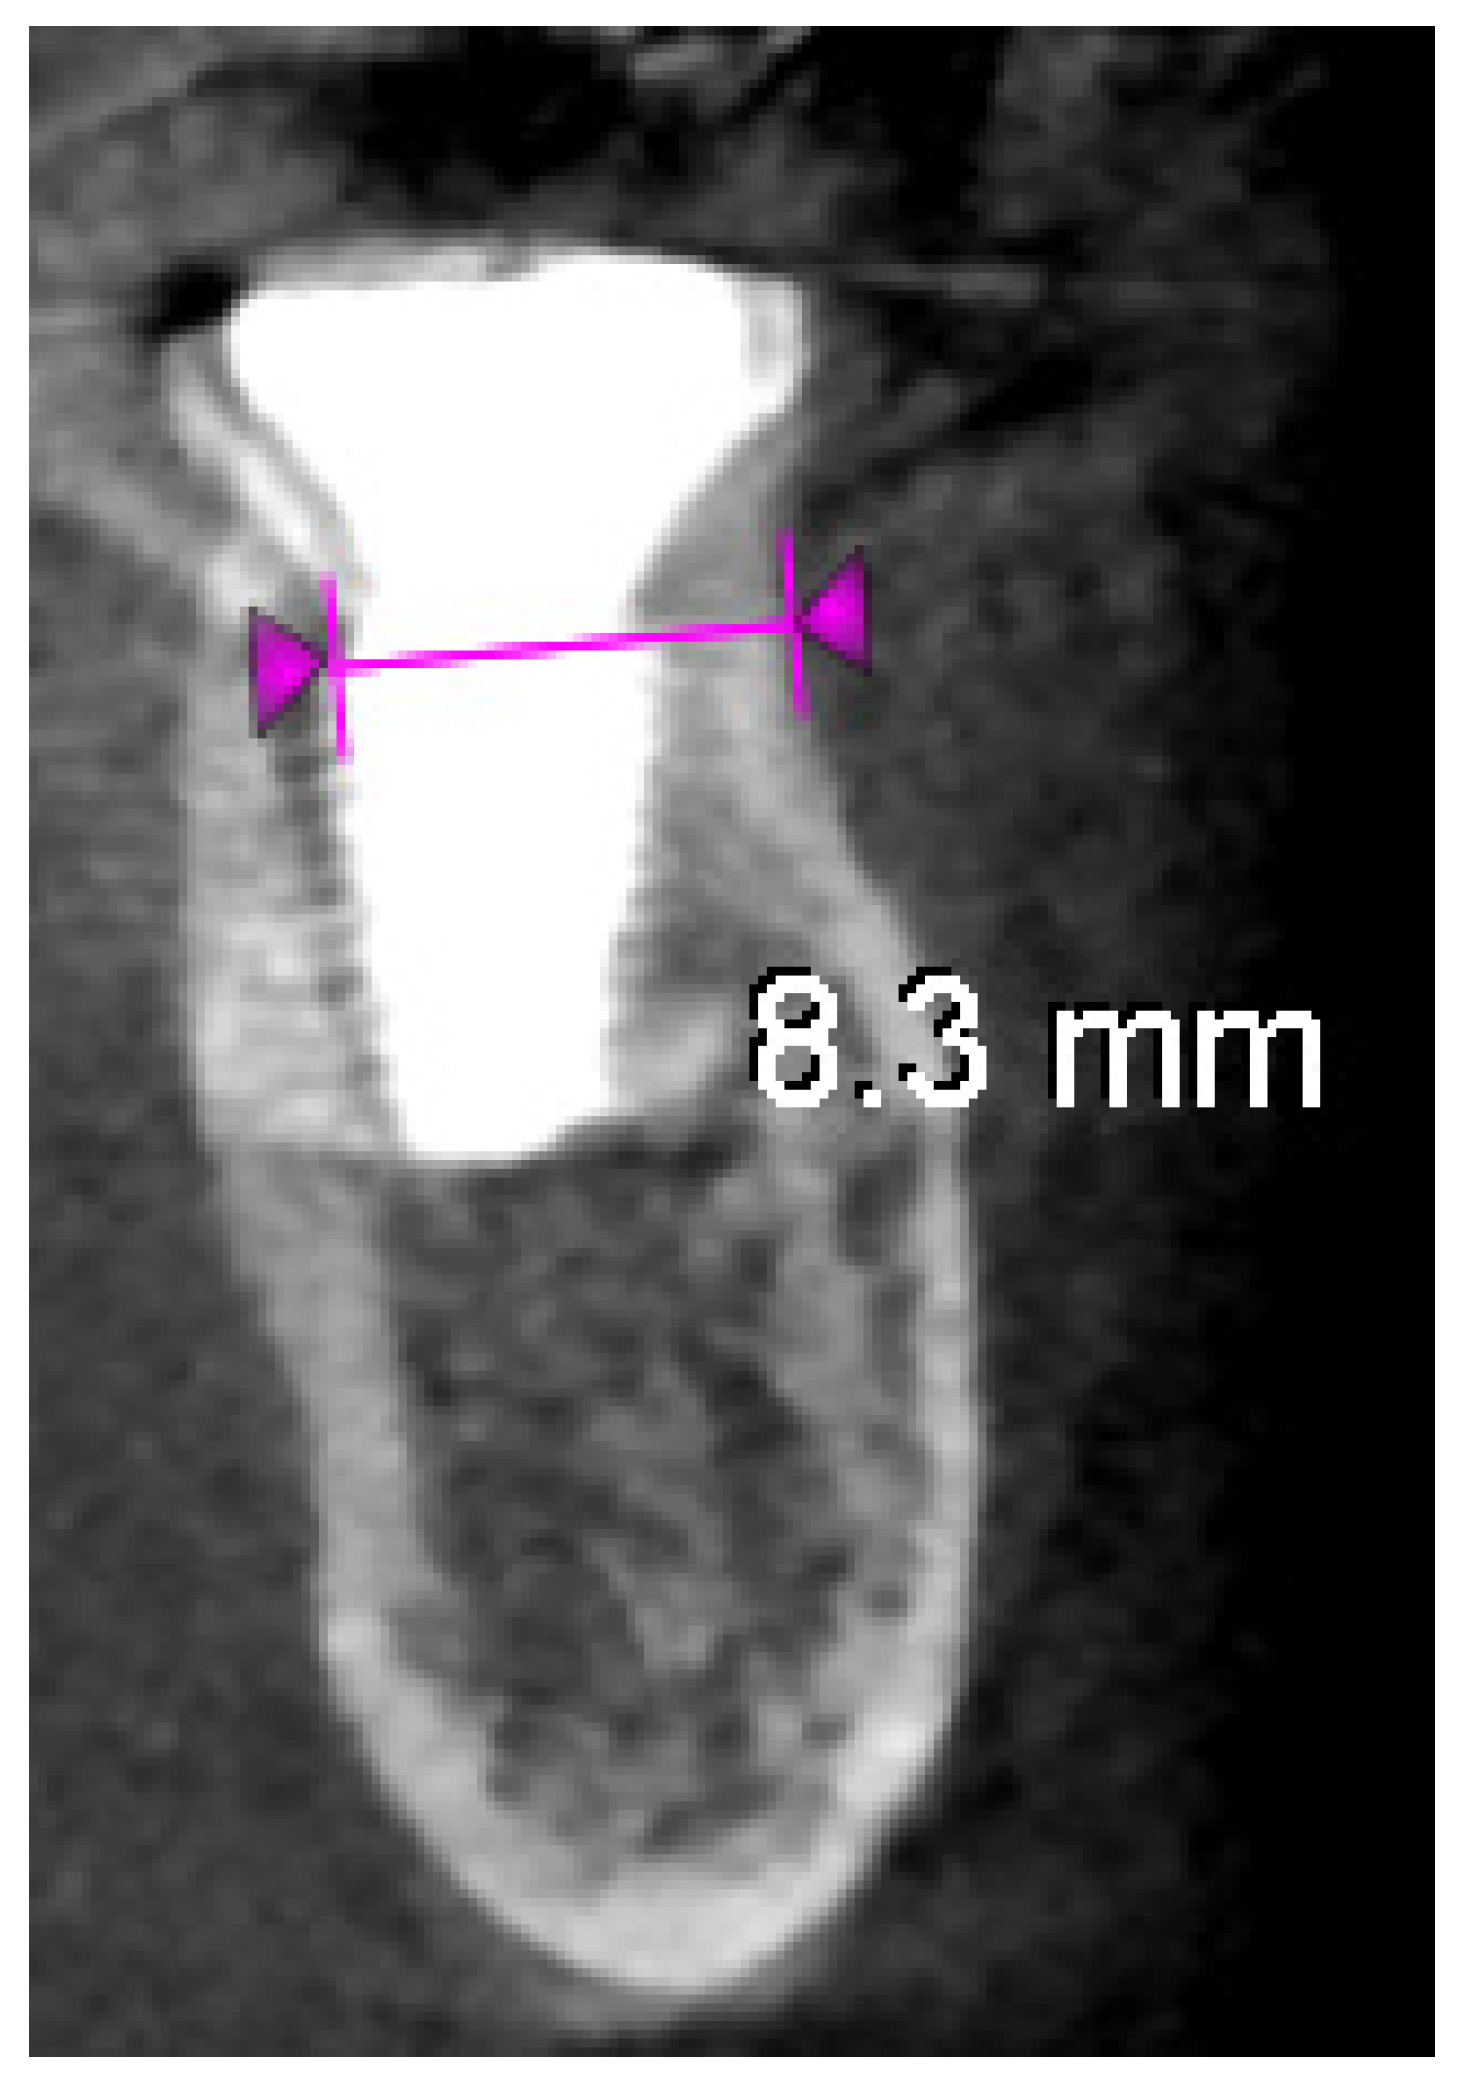

- Immediate post-op imaging: A postoperative CBCT scan was obtained to evaluate the implant position and to measure the alveolar ridge dimensions after implant placement (Figure 6). CBCT confirmed that the implant was accurately centered in the socket.